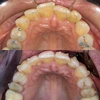

Diş Çapraşıklığı

Diş ve Diş eti hastalıkları